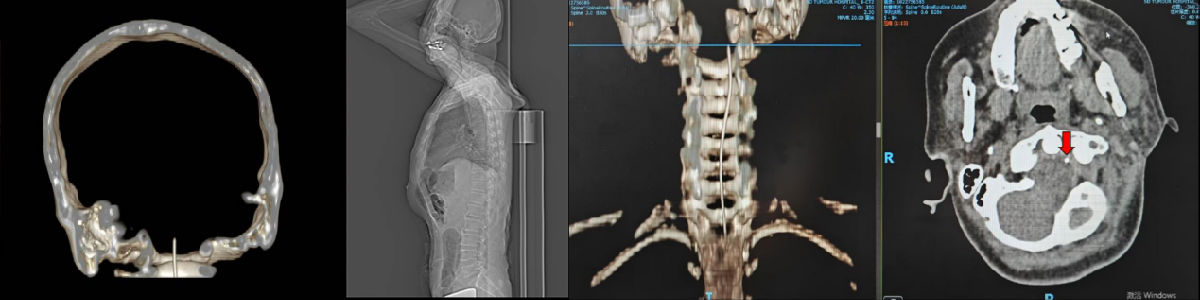

术中定位鞘内泵导管尖端位于枕大池

术后复查鞘内泵导管尖端位于枕大池